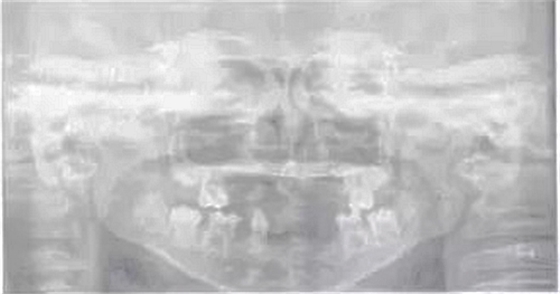

頜面斷層檢查:運用數(shù)字放射影像技術(shù)評估患者缺牙區(qū)牙槽嵴和下頜骨解剖狀況,追問病史,患兒家長否認近親結(jié)婚史及家族史。診斷為:(1)小兒軟骨外胚層發(fā)育不全綜合征;(2)牙列缺損。就診后,行全面口腔檢查,取模,制作研究模型。經(jīng)與患者協(xié)商溝通,采用覆蓋義齒修復(fù)。

圖1患兒曲面斷層片